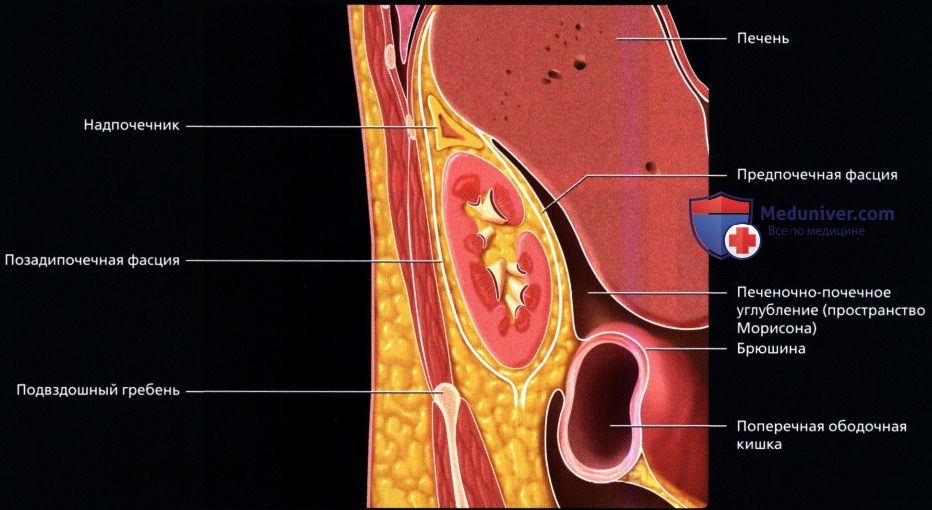

а) Анатомия почек:

2. Топографическая анатомия почки:

• Лежат в забрюшинном пространстве, окружены почечной фасцией (фасция Героты)

• У взрослого каждая почка около 9-14 см в длину и 5 см в ширину

• Обе почки лежат «на» квадратных мышцах поясницы, латеральнее поясничных мышц

б) Лучевая анатомия почки:

• Забрюшинные структуры бобовидной формы с четким контуром, смещающиеся при дыхании